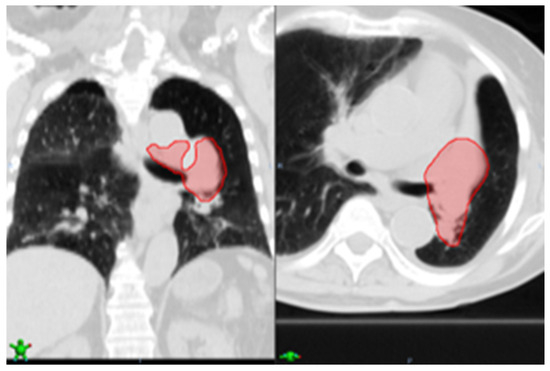

Figure 4 shows a sample case (Case ID 4), where the nodule detection algorithm detected and classified seven nodules as malignant. Out of the seven nodules, three were found in the right inferior lobe (RIL), two were found in the left inferior lobe (LIL), and two in the left upper lobe (LUL). According to the EHR-extracted information, however, the confirmed tumors were in LUL. Using this information, the result is automatically refined, and the FPs are removed.

Figure 4. Showing an example case of EHR-guided tumor auto-segmentation where the extracted information regarding the confirmed tumor is used to remove FPs. The nodule detection algorithm detected and classified seven nodules (red circles) as malignant for this sample case (Case ID 4). Out of the seven nodules, three were found in the right inferior lobe (RIL, left red box), two were found in the left inferior lobe (LIL, middle red box), and two in the left upper lobe (LUL, right green box). According to the EHR-extracted information, however, the confirmed tumors were in LUL. Using this information, the result is automatically refined, and the FPs are removed.